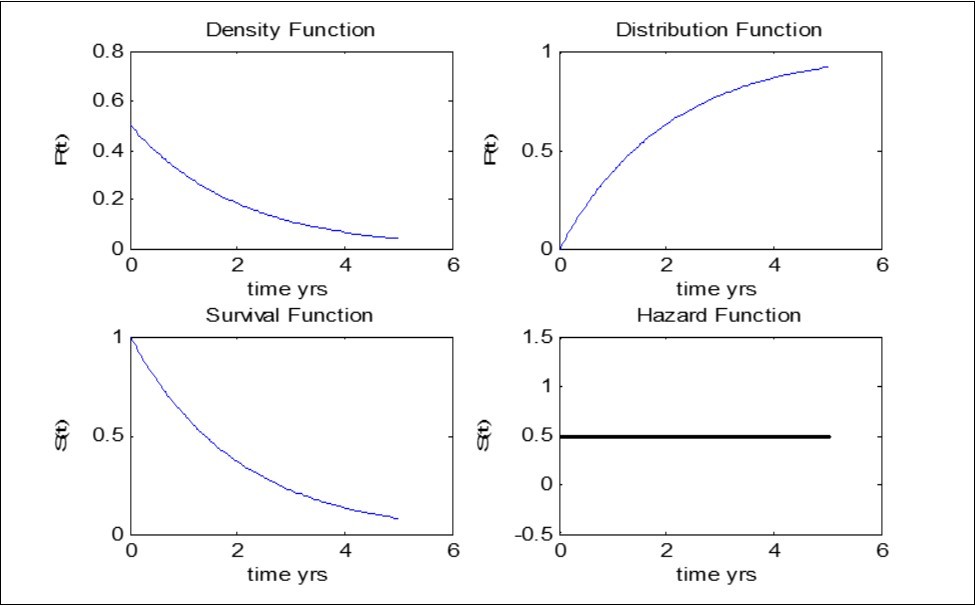

From the survival graph below (Figure 3), we can see that the hazard rate for Exponential distribution is constant over time. This means that on average 0.5 events will occur per individual at risk per month (during a period in which the hazard remains constant at this value). The survival rate for exponential declines monotonically with time (i.e the risk of a child dying decreases with time)

We can infer that the risk of death occurring among Under-five children decreases with time. This situation is referred to as Negative Duration Dependence.

Figure 3.Data Analysis and Validation of Result - Exponential Model